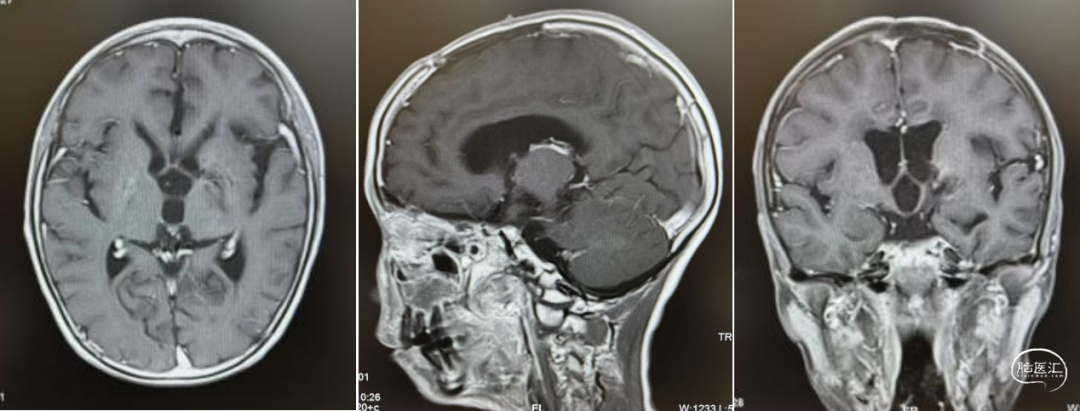

经儿童脑肿瘤MDT讨论后,考虑生殖细胞肿瘤,建议先化疗再放射治疗。1疗程后病变明显退缩。结疗后复查,肿瘤基本消失。此后3年予以定期复查未见复发。

结疗3年后随访

儿童松果体区生殖细胞肿瘤患者中男性多见。该区域肿瘤由于早期即可压迫中脑导水管,常以梗阻性脑积水为首发表现。对于怀疑生殖细胞瘤者,可以考虑化疗消除肿瘤进而缓解脑积水。而对于非生殖细胞瘤性生殖细胞肿瘤我们已有多例汇报此处不做赘述。对于例2患者,综合已有临床资料,经儿童脑肿瘤MDT团队会诊后认为可以考虑化疗,第一疗程化疗后即看到肿瘤明显退缩。证实肿瘤对化疗有效。完成后续治疗后肿瘤基本消失。后续予以定期观察,且有进一步退缩迹象。